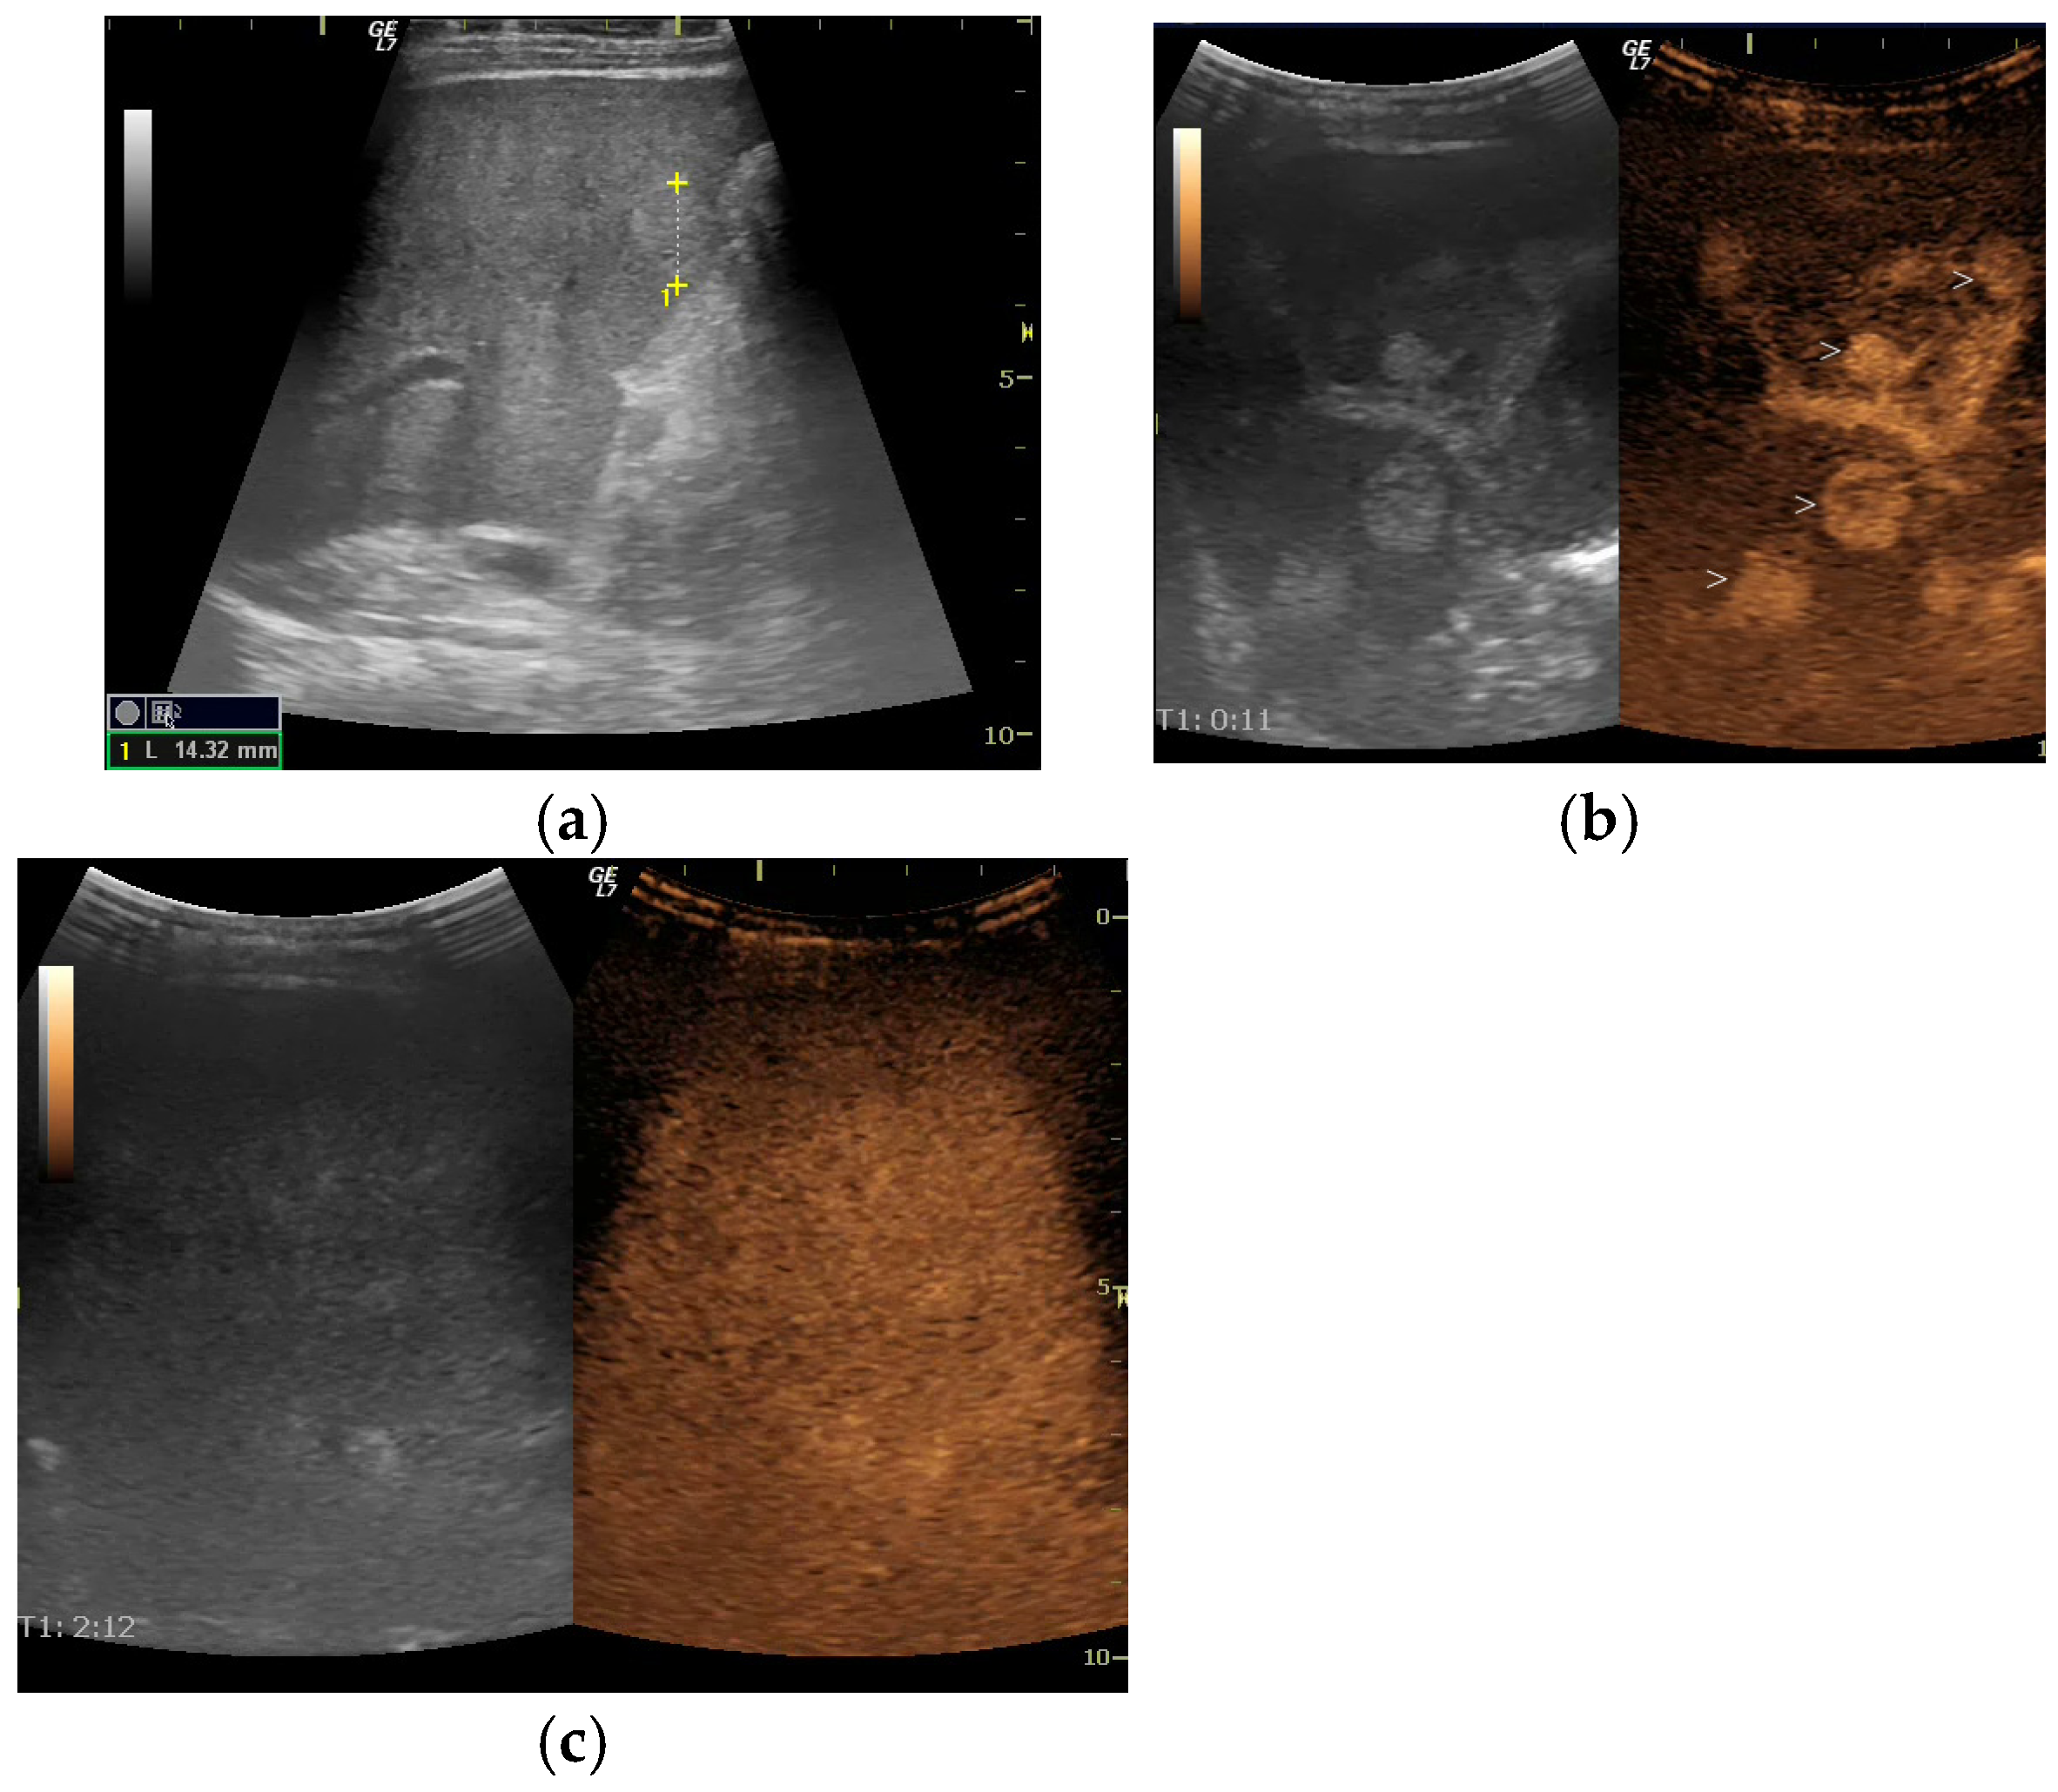

Remarkably, under anti-TNF treatment, there has been a significant improvement in liver lesions, as evidenced by reductions in both their size and number on repeated liver imaging (Figure 3 and Figure 4), along with normalisation of GGT levels in subsequent years. Improvement was evident after just one year of treatment and continued to progress until the patient reached 17 years of age. Splenomegaly persisted without evidence of portal hypertension, and liver stiffness on elastography decreased slightly over time (6.1 kPa before Etanercept and 5.6 kPa after treatment).

Figure 3. Ultrasound (US) evaluation after 9 years of Etanercept treatment. (a) B Mode US shows no evident liver nodules; (b) Contrast-enhanced ultrasound (CEUS) arterial phase shows an inhomogeneous pseudonodular enhancement of the right lobe; (c) CEUS in parenchymal phase—no hypoenhanced nodules are seen.